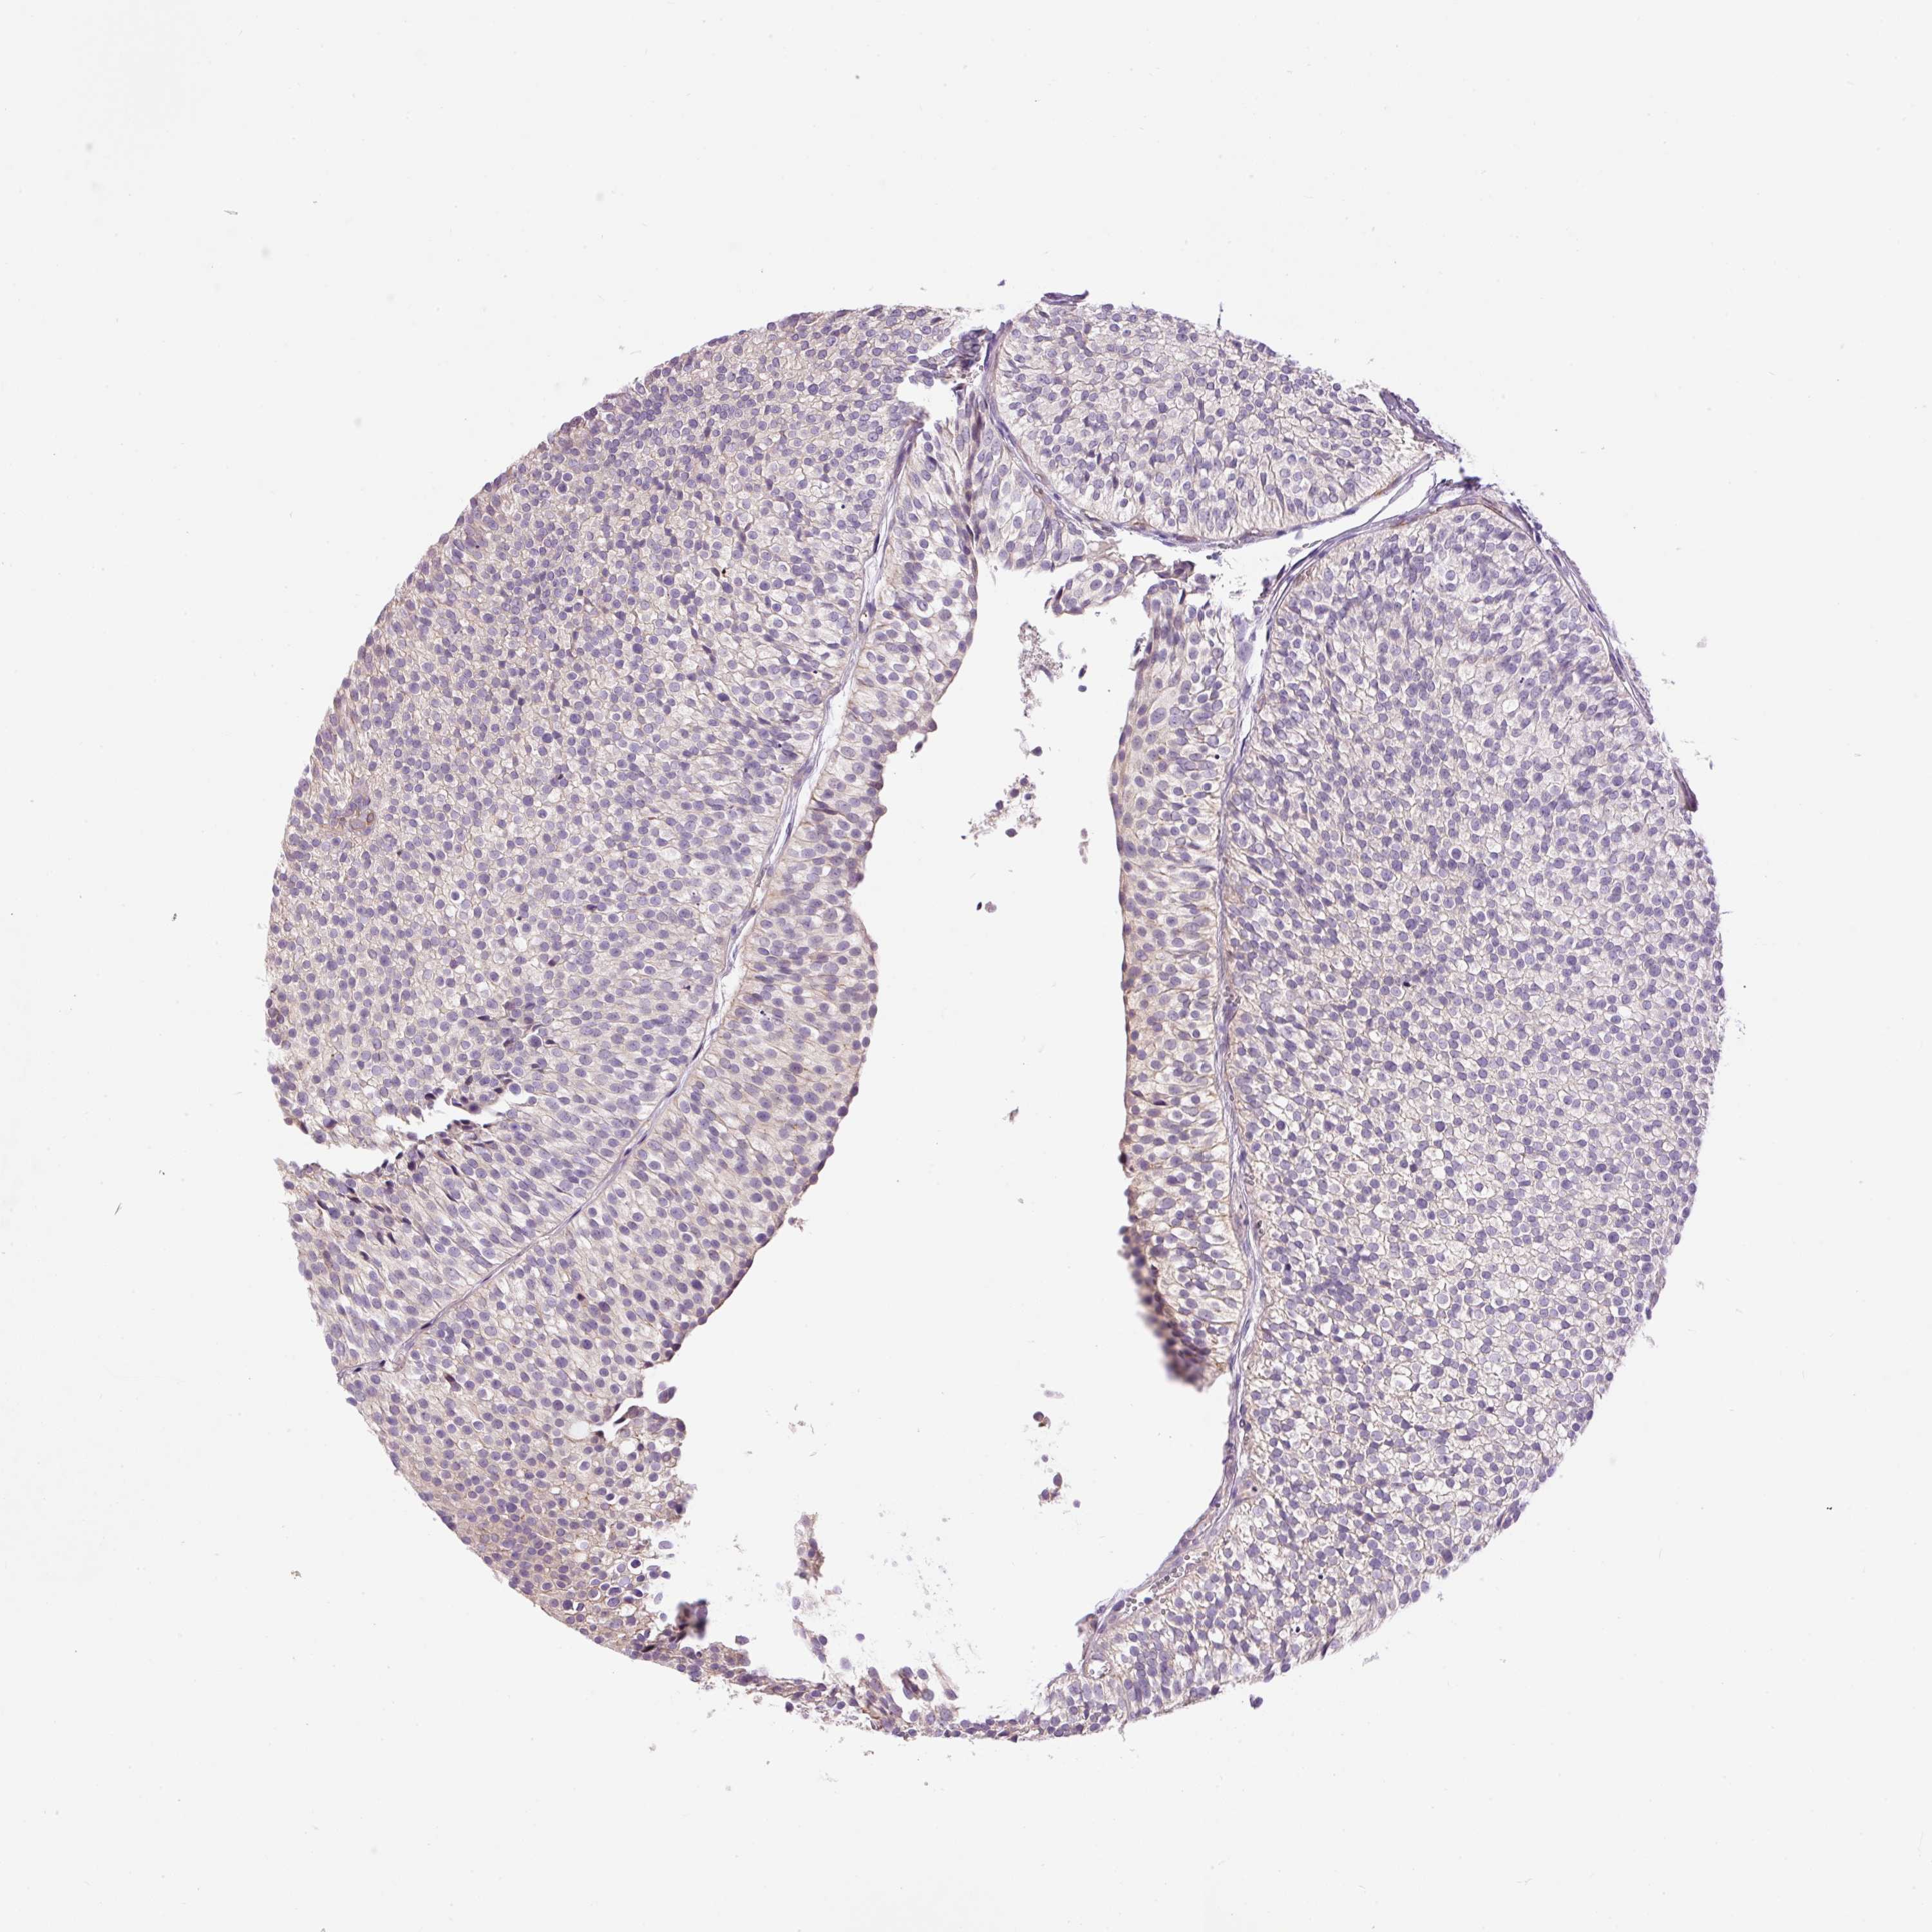

UROTHELIAL CANCER - Protein expressioni

A mouse-over function shows sample information and annotation data. Click on an image to view it in a full screen mode. Samples can be filtered based on level of antibody staining by selecting one or several of the following categories: high, medium, low and not detected. The assay and annotation is described here.

Note that samples used for immunohistochemistry by the Human Protein Atlas do not correspond to samples in the TCGA dataset.

Antibody stainingi

Antibody staining in the annotated cell types in the current human tissue is reported as not detected, low, medium, or high, based on conventional immunohistochemistry profiling in selected tissues. This score is based on the combination of the staining intensity and fraction of stained cells.

Each image is clickable and will lead to virtual microscopy that enables deeper exploration of all samples and also displays staining intensity scores, fraction scores and subcellular localization as well as patient and tissue information for each sample.

Antibody HPA050409

Antibody HPA054211

Urothelial carcinoma, Low grade

Urothelial carcinoma, High grade

Urothelial carcinoma, NOS